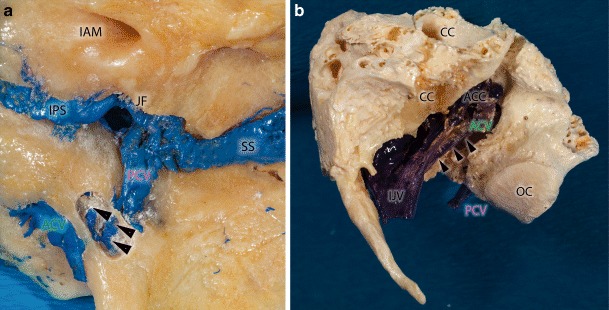

Fig. 2.

Macerated bony specimens presenting the lateral suboccipital region with preserved veins (filled with blue color). a Medial surface of the petrous bone on the right side. In this special case we could observe a venous connection between the anterior and posterior condylar vein. The bony canal of this bridging vein was drilled from medial (arrowheads). ACV anterior condylar vein, IAM internal auditory meatus, IPS inferior petrosal sinus, JF jugular foramen, PCV posterior condylar vein, SS sigmoid sinus

In two of the 40 examined cadaveric samples we could verify a bony communication between the HC and CoC within the occipital condyle with a small venous anastomosis connecting the intracondylar portions of the ACV and PCV (Figs. 2a and 3c). In two other cases the ACV drained directly into the internal jugular vein bypassing the ACC and the SJB (Figs. 2b and 3b).